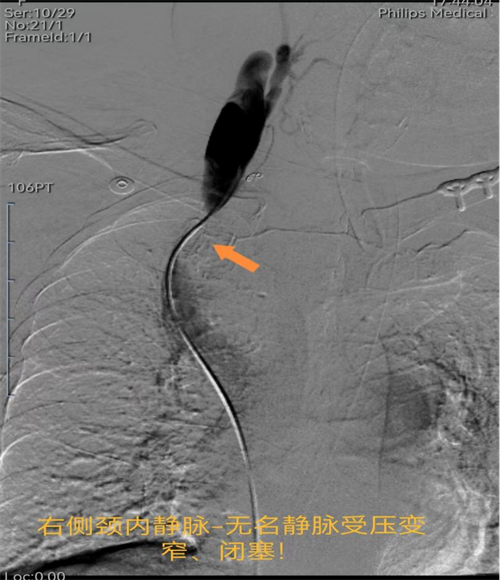

据了解,李奶奶曾被诊断患有胸腺瘤,多次前往四川省人民医院及四川大学华西医院就诊。由于其身体基础状况较差,且肿瘤巨大(已侵犯大血管及气管),外科切除难度极大,手术风险极高,李奶奶本人也拒绝外科手术切除。此次,因巨大的胸腺肿瘤同时压迫气道和右侧无名静脉,导致李奶奶出现急性呼吸困难和上腔静脉血液回流受阻而昏倒。

多科携手,为患者开启“生命之路”。手术由介入医学科和麻醉科协同完成。介入医学科副主任许泽兵带领介入团队在DSA机下精细操作,麻醉科全力保驾护航,手术有序推进,团队配合默契,无缝衔接。术中,先对肿瘤进行精准治疗(动脉灌注化疗栓塞),促使肿瘤坏死缩小;接着在右侧上腔静脉安置血管支架,解除肿瘤所致上腔静脉梗阻;最后在气管内安置气道支架,解除肿瘤所致气管梗阻,手术过程十分顺利。术后,李奶奶被转入重症医学科,经重症团队精心治疗,患者术后恢复良好。